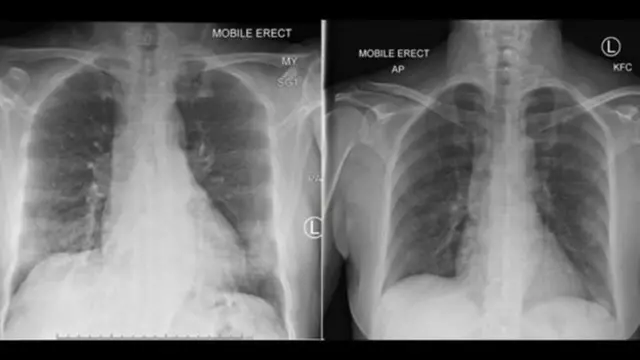

Ўзбекистонда коронавирус юқтирганлар сони бир минг атрофида экан, кўпчилик бу 34 миллионли мамлакат учун катта эмас, дейишади.

Covid-19 касалидан ўлганлар ҳам ҳозирча расман тўрт киши.

Бу эса дунёдаги ўртача 1-2% ўлимдан ҳам анча паст, ҳатто 0.5% ҳам эмас. (13.04.2020 ҳолати).

Ўзбекистонда тиббий хизматнинг аянчли ва ёмон аҳволда эканлиги, миллионлаб фуқаро чет элларда ишлаётгани, жамиятда ҳам ўзини иҳоталаш одати азалдан бўлмагани ҳисобга олинса, рақамлар жуда баланд бўлиши ҳам мумкин эди.

Лекин Ўзбекистонда (ва аксар собиқ Совет давлатларида) чақалоқларга мажбурий БЦЖ вакцинаси қилинади.

Ҳозир олимлар айнан БЦЖ мажбурий бўлган мамлакатларда коронавирус юқиши ва ундан ўлиш ҳоллари нега анча кам, деган саволга жавоб излашмоқда.